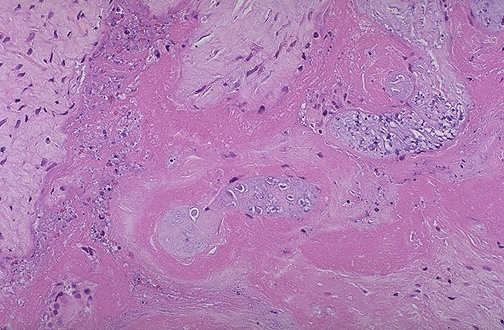

Microscopically, this placental infarct demonstrates

pale, necrotic chorionic villi

.